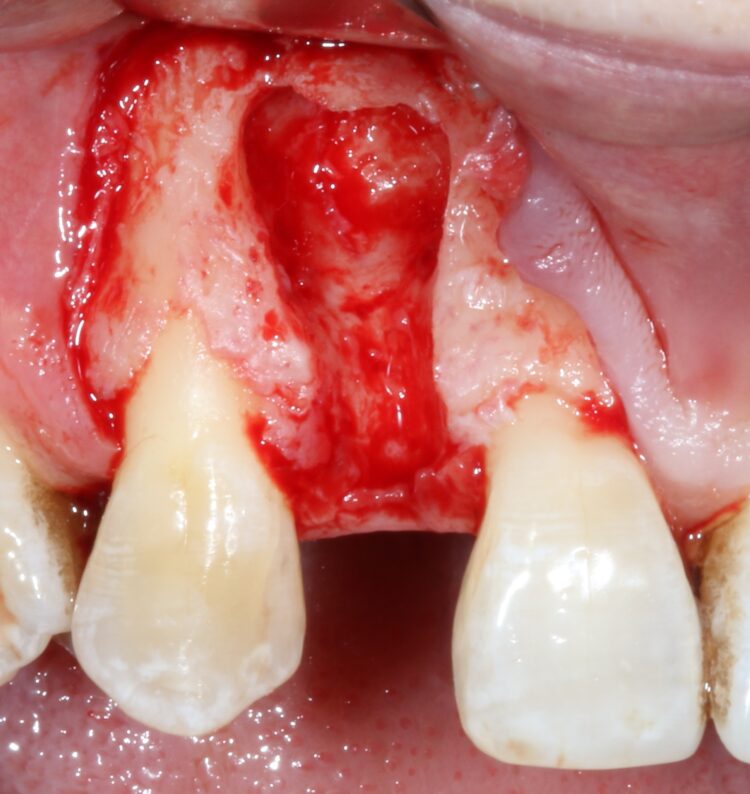

The first treatment phase included the elevation of a large full thickness flap to fully expose the area and enable the harvesting of autogenous bone utilising a safescraper.

The UR2 was then removed including excavation of all granulation tissue, taking care to avoid any direct curettage of the exposed UR3 root. The large bone defect was then filled with a 50/50 mix of autogenous bone chips and an allograft (MinerOss®, a cortico-cancellous mix – BioHorizons Camlog) and the buccal defect was covered with a native porcine collagen membrane with a high percentage of collagen type III for a prolonged barrier function of six months. No fixation pins were used.

The concept was that this exposed membrane would provide a barrier and prevent loss of the bone graft, but would also break down rapidly, favouring early epithelialisation of the open wound by secondary intention healing.

The occlusal aspect of the bone graft – which would remain exposed during the healing period – was covered with a shorter acting native collagen membrane. The concept was that this exposed membrane would provide a barrier and prevent loss of the bone graft, but would also break down rapidly, favouring early epithelialisation of the open wound by secondary intention healing.

The muco-periosteal flap was sutured back with 6.0 Prolene and no attempt was made to coronally advance the flap for complete closure. The rationale was to maintain the open socket wound and thereby preserve the original mucogingival relationship with no alteration. The socket entrance was sealed with the short acting membrane, while the original tooth (after root removal) was utilised as a temporary pontic and bonded to the adjacent teeth with flowable composite.